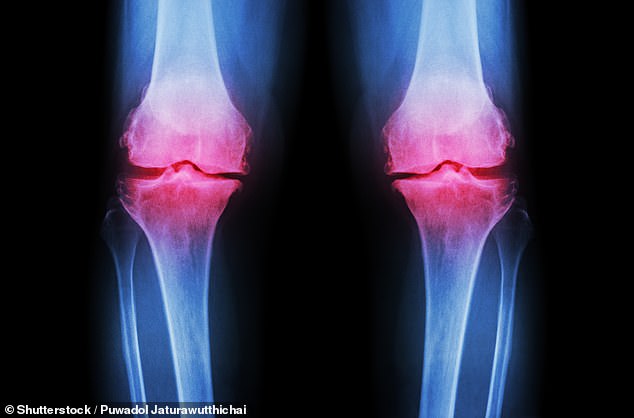

The 40s mark a turning point in how the body processes food, increasing the risk of cardiovascular disease later in life. The Stanford study found that shifts in lipid metabolism make it harder for the body to process fats and sugars as we age, leading to higher cholesterol levels. This can cause cholesterol to build up in arteries, raising blood pressure and straining the heart. Foods high in saturated fats, such as processed meats and fried goods, pose particular risks. At the same time, bone health begins to decline. The Royal Osteoporosis Society (ROS) reports that peak bone health occurs at 30, and by 40, people are at risk of developing osteopenia, a precursor to osteoporosis. Up to 40% of those over 50 may have this condition, with one in two women and one in five men over 50 facing a fracture due to osteoporosis.

Prevention is critical, according to experts. Professor Hamish Simpson of Queen Mary University of London notes that osteopenia is often silent until a fracture occurs. 'Eating well, reducing alcohol intake and increasing exercise can all reduce the risk of falls and fractures in later life,' says Dr. Richie Abel of Imperial College London. He recommends a calcium-rich diet, especially from food sources, and vitamin D supplements. For bones, loading exercises like jumping or skipping are most effective, as they stimulate growth through small shocks.